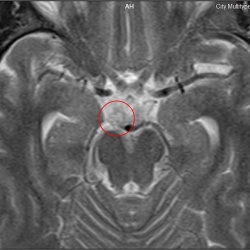

Здравствуйте, подскажите, пожалуйста, по такому вопросу: я делал МР-ангиографию головного мозга (подозрение на вертебробазилярную недостаточность), на одном из снимков заинтересовала одна область (не относящаяся к сосудам) - пятно, которое можно рассмотреть только при увеличении. Является ли это пятно какой-либо патологией, или это вариант нормы?

Виталий60, область которую вы обвели кругом на картинке - либо эффект суммации (срезы идут обычно по 5 мм  и  наш мозг не хочет быть строго паралельным данным срезам), либо артефакт от тока ликвора. В общем - не вижу повода для беспокойства.

Потоковые артефакты в цистерне от пульсации основной артерии.

Да. У детей обычно это даже ещё сильнее выражено.